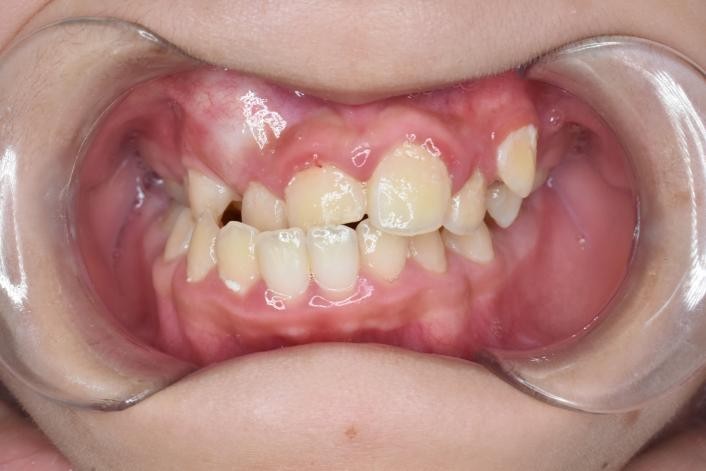

4.牙弓不对称

(图为单侧后牙反合一期矫治前后对比)

下图为早期矫治前后面型和口内像对比,可以看到矫治后的患儿面型左右基本对称,下牙列的偏斜程度也明显改善,前牙的反合得到解除,去除了上颌骨发育的不利因素。接下来就是等待患儿换完牙以后进行二期治疗,二期治疗可以从三维方向上控制牙齿的移动方向,进一步平衡咬合,使得矫治效果更加稳定。二期治疗的矫治器可以选择固定矫治器也可以选择无托槽隐形矫治器。

口腔正畸科主任张苗苗教授认为就牙弓不对称的患儿而言,上颌扩弓的时机应在生长发育高峰期或者生长发育高峰期前进行干预,越早干预效果越好。有研究表明长期的未经治疗的单侧后牙反合,晚干预的患儿(CS4期)较早干预的患儿(CS1期)双侧下颌升支的差异会增加1倍,也就是说如果早干预的患儿面下部左右不对称值为2mm,那么晚干预的患儿面下部左右不对称值就要达到4mm。因此,如果您家的孩子存在牙弓不对称,就要赶在生长发育高峰前尽早的扩弓,甚至在乳牙期(CS1)就要开始。张主任呼吁广大市民朋友切不可相信某些不良的宣传,一定要选择正规医疗机构进行矫治,避免错过最佳的治疗时机。选择适当的矫治时机、正确的矫治方案使得正畸治疗事半功倍!